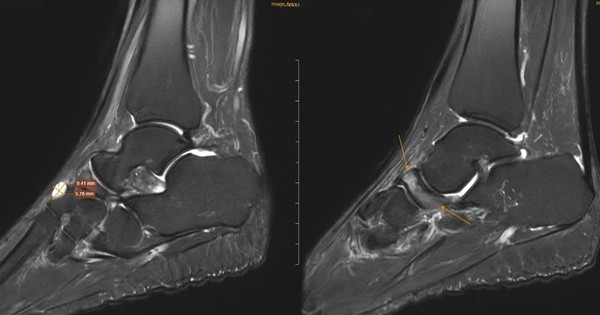

Đi khám vì đau cổ chân không rõ nguyên nhân, nữ giáo viên phát hiện ra xương bên trong đang bị tự hủy.